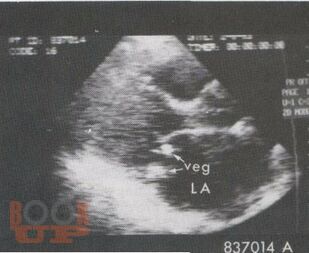

Инфекционный эндокардит

В настоящем учебном пособии освещены вопросы современных представлений об инфекционном эндокардите: определение, классификации, основные принципы диагностики и лечения. Имеются тестовые задания и ситуационные задачи для самоконтроля знаний.